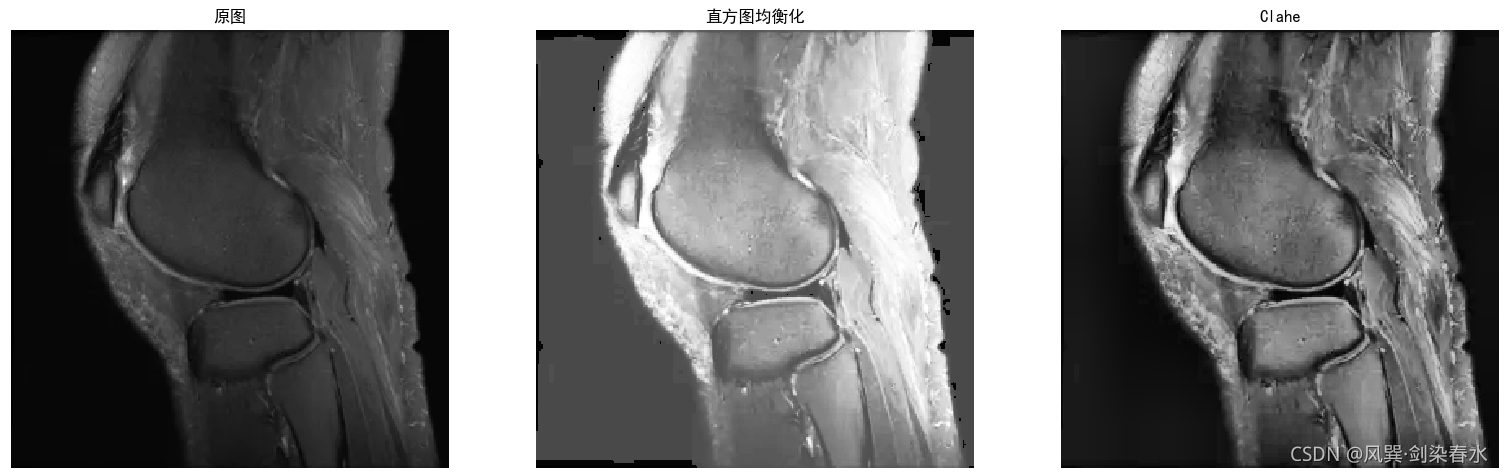

2.灰度图

from PIL import Image

import matplotlib.pyplot as plt

import numpy as np

import cv2

test = Image.open('./tupian/test4.png').convert('L')

test = np.uint8(test)

test_hist = cv2.equalizeHist(test)

clahe = cv2.createCLAHE(clipLimit=4, tileGridSize=(10,5))

test_clahe = clahe.apply(test)

plt.figure()

plt.subplot(1,3,1),plt.imshow(test, 'gray')

plt.axis('off'),plt.title('原图')

plt.subplot(1,3,2),plt.imshow(test_hist, 'gray')

plt.axis('off'),plt.title('直方图均衡化')

plt.subplot(1,3,3),plt.imshow(test_clahe, 'gray')

plt.axis('off'),plt.title('Clahe')

plt.show()